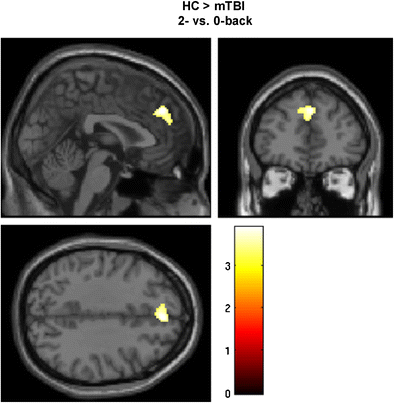

Working memory activation patterns for healthy controls (HC) and patients with mTBI (p uncorrected < 0.001, cluster-level FWE-corrected p < 0.05)

Differences in working memory activation between HC and patients with mTBI during high working memory load. In mTBI patients, a significant cluster of lower activation was found within the medial prefrontal cortex (peak MNI-coordinates: 2, 44, 36) compared to HC (p uncorrected < 0.001, cluster-level FWE-corrected p = 0.045)

For the 1- vs. 0-back and 2- vs. 1-back contrasts, no differences were found between mTBI patients and HCs. Furthermore, F-tests did not reveal significant effects of subgroup. These results remained non-significant after exclusion of patients without detailed task accuracy data.

This is the first study that assessed the relationship between brain network function, WM performance and post-concussive complaints in the sub-acute phase after mTBI. In the total group of patients with mTBI, lower activation was found within the medial prefrontal cortex during high WM load, despite normal task accuracy and reaction times. Regarding subgroups, ICA revealed that DMN function and the interaction between the DMN and FEN were different between patients with and without post-concussive complaints. Altogether, these results might provide new insights into the concept of mTBI and post-concussive complaints.

So far, several studies have investigated WM performance in mTBI, with varying results (Bryer et al. 2013; Mayer et al. 2015a). In general, stronger activation was observed during high task difficulty compared to healthy controls, which could indicate increased mental effort to maintain normal task accuracy, leading to mental fatigue (McAllister et al. 1999; McAllister et al. 2001; Smits et al. 2009). Moreover, with increasing task difficulty patients with mTBI were not able to sufficiently recruit brain areas for WM performance, which was reflected by lower activation compared to controls (McAllister et al. 2001). However, this finding mostly pertains to lateral prefrontal and parietal areas and the supplementary motor area. In the present study, we demonstrated lower activation within the medial prefrontal cortex during high WM load in mTBI patients compared to healthy controls. This region is important with respect to executive functioning, but also with regard to emotion regulation (Euston et al. 2012; Messina et al. 2015). Furthermore, the medial prefrontal cortex is a core area of the DMN and an important relay station in the interaction between the DMN and other (executive) brain networks (Buckner et al. 2008; Seeley et al. 2007). Our findings may thus reflect stronger deactivation of the DMN during working memory performance. Since the prefrontal cortex is often affected by TBI, it can be hypothesized that changes in function of the medial prefrontal cortex are related to post-concussive complaints and emotion regulation deficits after mTBI (van der Horn et al. 2015). In particular, dysfunction of this area may lead to impaired dynamics between the DMN and executive networks, resulting in cognitive and affective complaints. Our network analyses revealed significant results that are in line with this hypothesis.